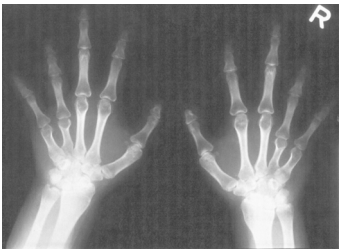

3 一位 1 天大的足月產男嬰,出生後被發現有先天畸型及心雜音。出生體重為 1.8 公斤,身長為 43 公 分,頭圍為 31 公分;肌肉張力強(hypertonia);其手腳之畸型如下圖所示。下列何者為最可能之診斷?

(A) Holt-Oram 症候群 (B) Trisomy 18 症候群 (C) Ellis-van Creveld 症候群 (D) Alagille 症候群